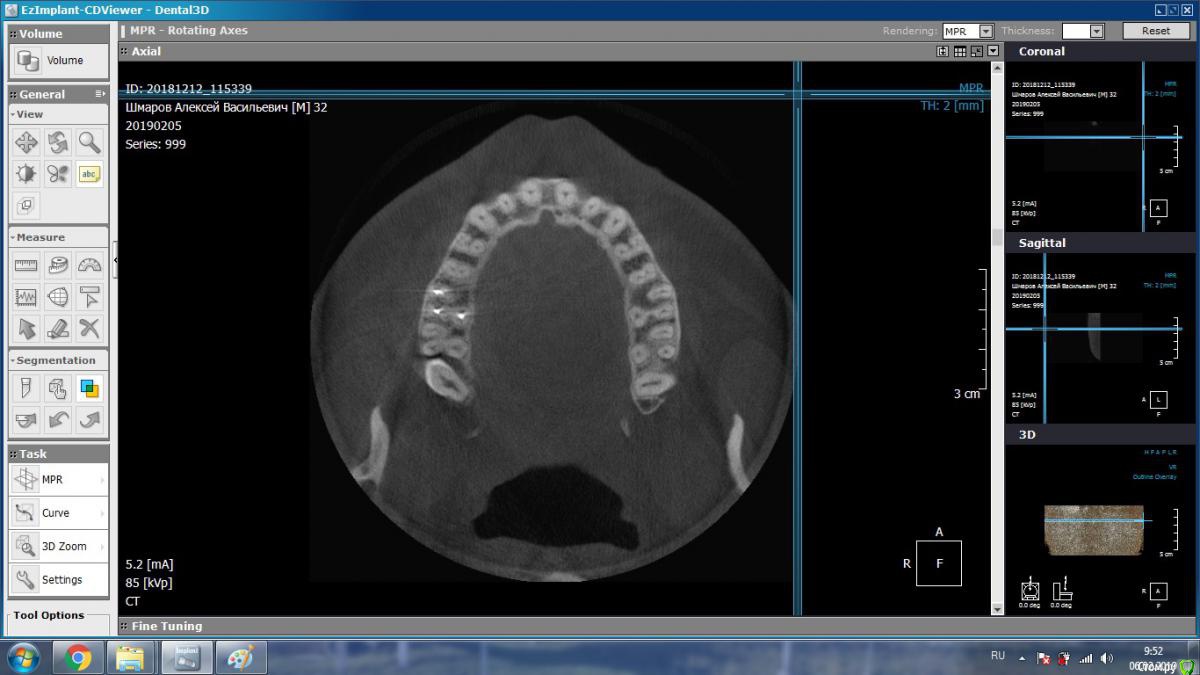

DmitrySH Опубликовано 5 февраля, 2019 Поделиться Опубликовано 5 февраля, 2019 Такие подойдут? В Аксиальной проекции покажите еще несколько срезов Ссылка на комментарий

aleks.k Опубликовано 6 февраля, 2019 Автор Поделиться Опубликовано 6 февраля, 2019 Срезы Ссылка на комментарий

aleks.k Опубликовано 6 февраля, 2019 Автор Поделиться Опубликовано 6 февраля, 2019 Еще один срез, может быть более удачный чем первые в этой проекции Ссылка на комментарий

DmitrySH Опубликовано 6 февраля, 2019 Поделиться Опубликовано 6 февраля, 2019 Срезы Очень хорошо. Теперь как первые три, но увеличить 16 зуб. Остальные нам мало интересны, пазуха тоже Ссылка на комментарий

DmitrySH Опубликовано 7 февраля, 2019 Поделиться Опубликовано 7 февраля, 2019 В шестом зубе похоже еще 1 канал есть Ссылка на комментарий